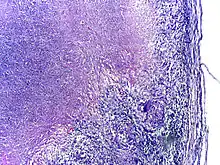

Microscopy of tuberculous epididymitis. H&E stain